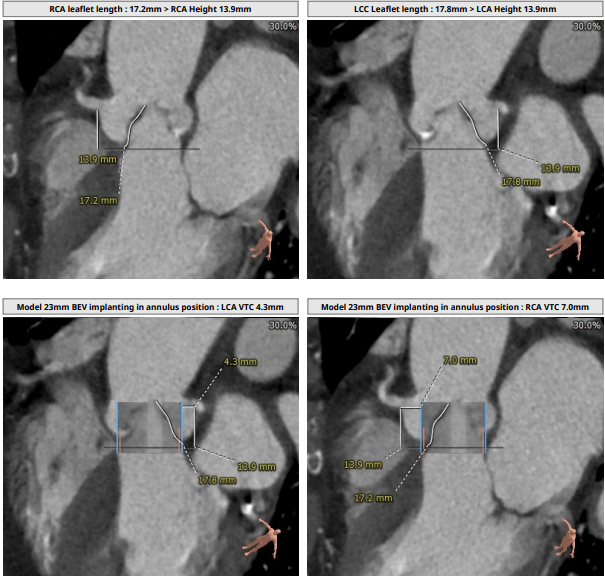

罕见结构,挑战极限|梧州市工人医院心血管内科彭军主任团队完成高冠脉

8mm ;rca 高度13.9mm,瓣叶长度17.2mm.考虑冠脉阻塞风险较高.